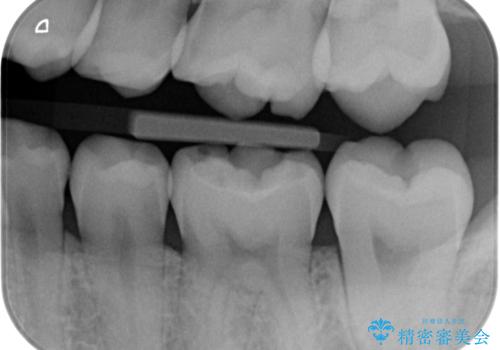

【歯に穴が空いている】ゴールドインレーで修復

- 歯に穴が空いているとの事で来院。

セラミック、ゴールドの詰め物のご案内をしたところゴールドを希望されたのでゴールドインレーで治療を行いました。